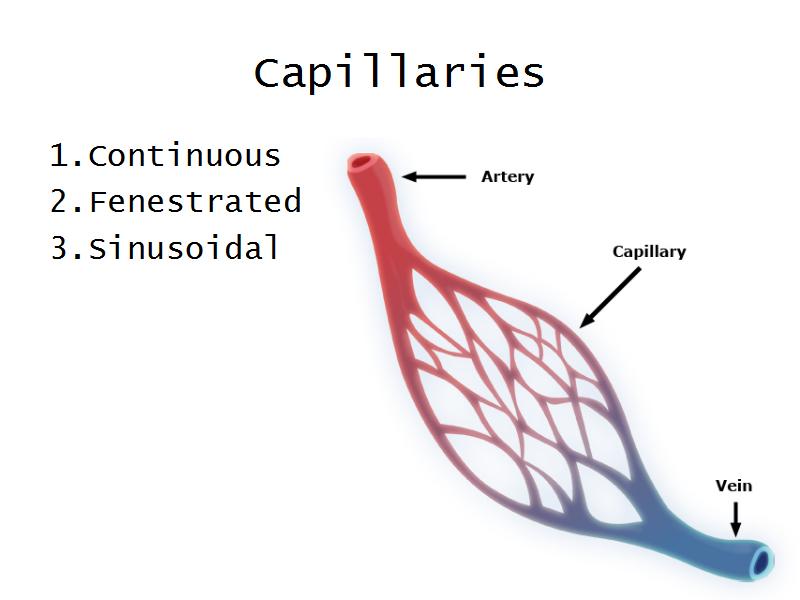

Pituitary gland

How does the pituitary and hypothalamus communicate?2 ways